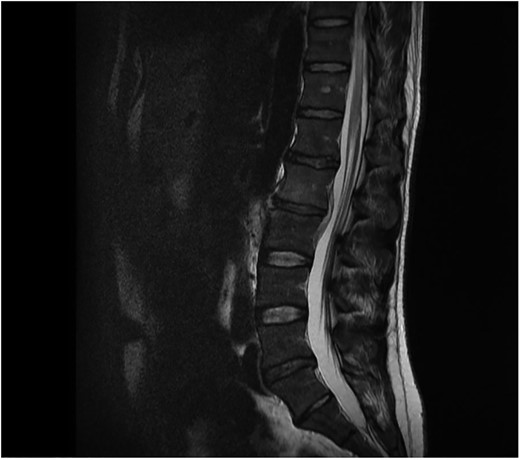

The initial chest and abdominal radiographs were normal but blood tests showed a raised CRP of 244, so broad spectrum antibiotics were started. It was decided that due to the abdominal pain and raised inflammatory markers the patient required a CT abdomen/pelvis which showed para-aortic lymph nodes but no other abnormalities. Testicular lymphatic drainage goes to the para-aortic lymph nodes, so they were examined and had an ultrasound scan which were both normal. Blood cultures grew Staphylococcus aureus and, after discussion with the microbiologist, an MRI spine was performed to rule out osteomyelitis. This showed L2/L3 osteomyelitis, epidural abscess and psoas inflammation (Fig. 1). The microbiologist also advised for a trans-oesophageal echocardiogram to rule out development endocarditis, which was normal. On further questioning, the patient had acupuncture treatment 2 weeks prior to admission for mechanical back pain. The treatment was performed by a trained physiotherapist and involved the insertion of sterile disposable needles into acupoints in the lower back to relieve pain.

Sagital T1 MRI lumbosacral spine. Osteomyelitis in L2 and L3 vertebral bodies, epidural abscess and inflammation of the psoas muscles.